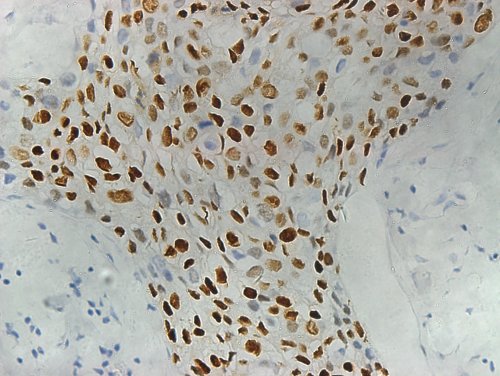

基因科技(上海)有限公司的產品“孕激素受體檢測試劑盒”(PR)獲得國家三類體外診斷試劑注冊證(國械注準20143402133)。

該產品孕激素受體檢測試劑盒(免疫組織化學法),Progesterone Receptor Detection Kit (IHC)的主要組成成分有: 試劑A—單克隆兔抗人孕激素受體工作液、 試劑B—空白對照試劑 、 試劑C—檸檬酸鹽修復緩沖液 (粉劑) (具體內容詳見說明書 )。 預期用途:試劑盒用于體外檢測經福爾馬林固定、石蠟包埋的人乳腺癌組織切片中孕激素受體。